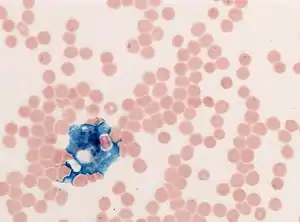

In histology, histopathology, and clinical pathology, Perls Prussian blue is a commonly used method to detect the presence of iron in tissue or cell samples.[1]: 235 [2][3][4] Perls Prussian Blue derives its name from the German pathologist Max Perls (1843–1881), who described the technique in 1867.[2] The method does not involve the application of a dye, but rather causes the pigment Prussian blue to form directly within the tissue.[5] The method stains mostly iron in the ferric state which includes ferritin and hemosiderin, rather than iron in the ferrous state.[6]

Perls's method is used to indicate "non-heme" iron in tissues such as ferritin and hemosiderin,[6] the procedure does not stain iron that is bound to porphyrin forming heme such as hemoglobin and myoglobin.[2] The stain is an important histochemical stain used to demonstrate the distribution and amount of iron deposits in liver tissue, often in the form of a biopsy.[6][7] Perls's procedure may be used to identify excess iron deposits such as hemosiderin deposits (hemosiderosis) and in conditions such as hereditary hemochromatosis.[8] Perls Prussian blue is commonly used on bone marrow aspirates to indicate levels of iron storage[4] and may provide reliable evidence of iron deficiency.[7]

Perls did not publish a detailed procedure other than indicating a dilute potassium ferrocyanide solution was applied to the tissue followed by hydrochloric acid.[2] Ferric iron deposits in tissue (present mostly as ferric iron within the storage protein ferritin) then react with the soluble ferrocyanide in the stain to form the insoluble Prussian blue pigment (a complex hydrated ferric ferrocyanide substance). These deposits are then visualizable microscopically as blue or purple deposits.[9]

Many methods of performing Perls Prussian blue stain for iron have been published, [2] Drury and Wallington (1980) give a protocol that uses a mixture of 1 part 2% hydrochloric acid and 1 part 2% potassium ferrocyanide that is applied to the section for 20–30 minutes followed by a rinse in distilled water and application of a counterstain such as eosin, safranin or neutral red.[5]